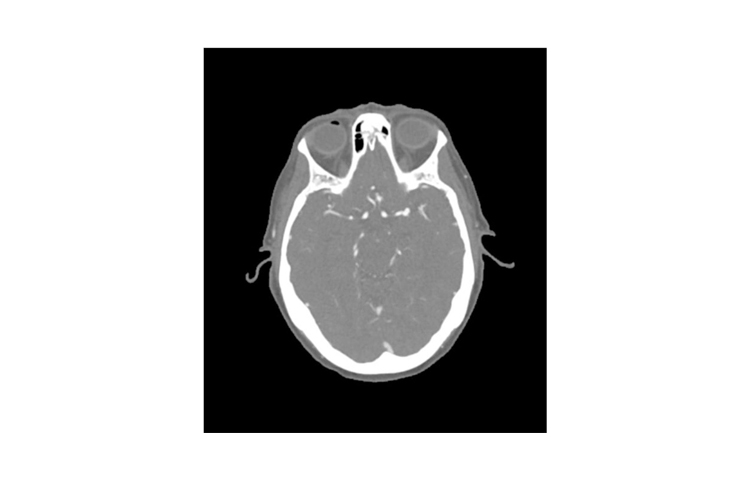

德國phantomx 50-03頭部CTA動脈瘤模體

德國phantomx 50-03頭部CTA動脈瘤模體模擬了在動脈期增強對比劑的頭部(CT 血管造影)。它從頂點到枕骨大孔。模體有三個顱內(nèi)動脈瘤,分別是中大腦動脈(MCA)、前交通動脈(ACoA)和基底動脈。

該模體可用于 CT(包括 CBCT)以評估和優(yōu)化成像性能及 AI 診斷。它也適用于培訓目的。模體提供了血管結構、軟組織和骨骼組織的詳細和逼真模擬,包括淋巴結等小細節(jié)。空氣空隙被約 -160 HU 的纖維素-聚合物復合材料填充。